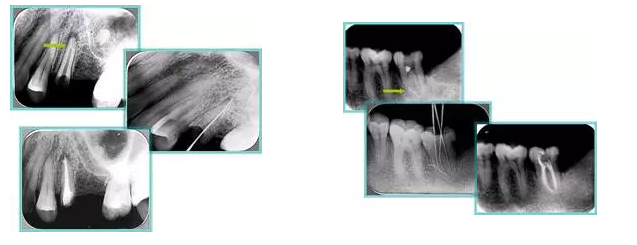

共有 4 張 X 線片,分別是術(shù)前、診斷絲 、主牙膠尖確認、術(shù)后。

( 1 )術(shù)前:術(shù)前 X 線片用來了解牙齒的大概情況。術(shù)前預(yù)期為多根牙時 X 線片應(yīng)偏頭拍攝。

( 2 )診斷絲:根據(jù)術(shù)前 X 線片進行開髓、根管的初步預(yù)備后,需要插入診斷絲,用來指示工作器械位置。常用 10 號或 15 號擴大器作為診斷絲插入牙髓腔。

( 3 )主牙膠尖確認:通過術(shù)前預(yù)期和診斷絲診斷,明確工作長度、牙根走向,進行根管預(yù)備。之后應(yīng)進行主牙膠尖(中銼)確認,已明確根管是否適合充填。

( 4 )術(shù)后:觀察治療效果。

左圖為根管充填術(shù)后 X 線片。圖中可見,根管充填較好。右下圖有白色小點,為側(cè)方加壓導(dǎo)致糊劑擠出所致,表明根管充填比較致密。

左圖和上圖為干髓治療后牙齒,齲齒疏通后進行根管充填。

如圖為塑化加根充處理后牙齒 X 線片。

常見有修復(fù)性鈣化和增齡性鈣化。下面為根管鈣化 X 線片。

右圖及下圖為器械折斷的 X 線片。箭頭處示折斷器械。